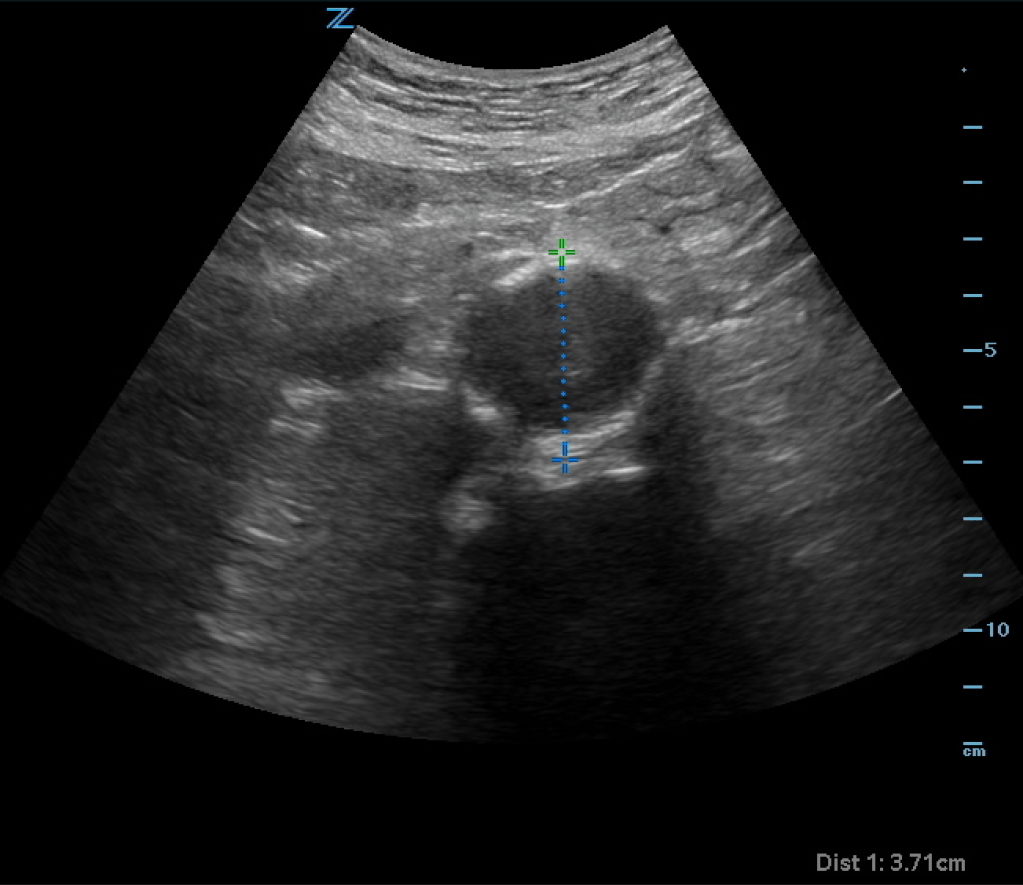

You obtain a bedside ultrasound:

The ultrasound shows an enlarged aorta concerning for AAA, measuring at 3.71cm. However looking closely at the aorta, it almost appears as if there is a dissection flap with potentially two lumens on the ultrasound. You obtain color doppler:

Color shows there are two areas in the aorta, one with flow and one with no flow concerning for potential dissection vs thrombus. CTA of the abdomen and pelvis is obtained and shows:

CT shows a AAA without rupture. There is an area of thrombus seen on the CT which correlates with the ultrasound findings seen above. There is no true dissection flap.

Remember that the aorta is retroperitoneal. Many times you will not actually see free fluid or evidence of rupture on ultrasound. A AAA on ultrasound plus abdominal pain is a ruptured AAA until proven otherwise. If you are concerned about dissection, you may see the flap and false lumen (color doppler may aid in the diagnosis) on ultrasound, but an ultrasound is not sensitive enough to rule out dissection. Obtain a CTA to evaluate the aorta. Also remember that thrombus is common in AAA and actually helps stabilize the aneurysm. In a normal caliper aorta however, thrombus should be considered evidence of underlying dissection (even if a dissection flap is not seen) until proven otherwise.

CTA of the abdomen/pelvis confirmed a 3.71cm AAA without rupture or dissection. Thrombus was visualized on the CT which explained the ultrasound findings. Vascular surgery evaluated the patient and recommended serial outpatient ultrasounds and cleared the patient for discharge.